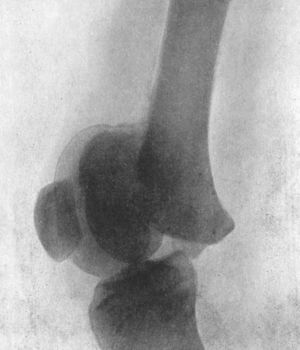

| 33. | Radiogram of Supra-condylar Fracture of Humerus in a Child | 81 |

| 34. | Radiogram of T-shaped Fracture of Lower End of Humerus | 83 |

| 35. | Radiogram of Fracture of Olecranon Process | 86 |